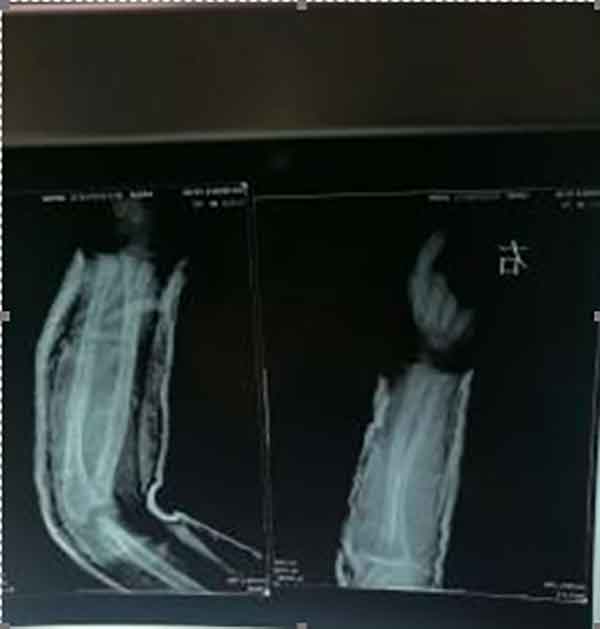

游智勇,男,15岁,电话13377708828,湖南临湘市黄盖镇广坪村新庄组人。五个月前外伤,右手腕关节脱臼,筋络萎缩,功能受限。右踝关节脱臼,功能障碍,右脚板向上受限,经多方治疗无果。于2020年5月31日入诊,经临床检查,游智勇右手腕脱臼和右踝关节脱臼,外伤所至右手脚关节筋络萎缩,引起右手脚同时行动受限,严重功能障碍。解决办法:1. 使用手法将右手脚关节同时扭正复位。敷用祖传研制药膏。同时,施以祖传中药。方一:红胡、桂枝、丹参、赤芍、青皮、条芩……方二:牛夕、木瓜、赤芍、荆芥、独活、续断、黄芪……方三:外用热敷:红花、桃仁、白芥、土别、牙皂、白芨、鬼箭羽……。

二个月后,经医者追踪调查:游智勇手脚恢复正常,患者监护人一致赞同曾令先医生治疗伤科后遗症手艺超强,医术精湛,医德高尚,值得医界弘扬。